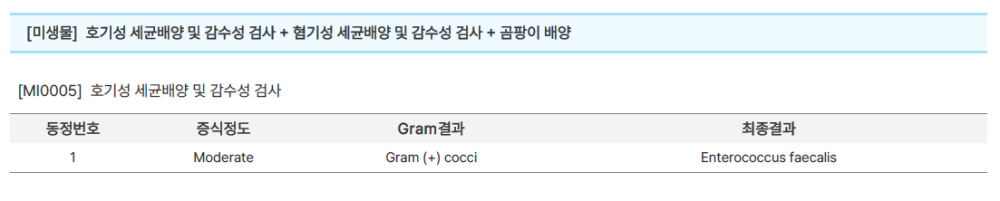

이후 배양검사를 통해 Enterococcus faecalis가 분리되면서, 최종적으로 간 농양으로 진단할 수 있었습니다.

해당 간 농양에서 추출한 농에서, 항생제 감수성 테스트를 진행하였고, 결과는 다음처럼 나왔습니다.

따라서, 감수성이 있는 Ampicillin과 vancomycin, Nitrofurantoin을 사용하였습니다.